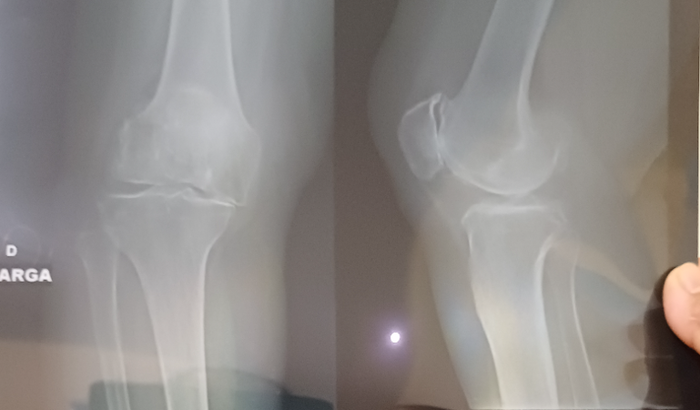

Eu sou Joelma , estou criando uma vaquinha para minha tia Terezinha em prol de uma cirurgia com urgência no joelho direito para incluir uma prótese devido artrose tricompartimental do joelho com degeneração meniscoligamentar nivel 5.  ver tudo

Eu sou Joelma , estou criando uma vaquinha para minha tia Terezinha em prol de uma cirurgia com urgência no joelho direito para incluir uma prótese devido artrose tricompartimental do joelho com degeneração meniscoligamentar nivel 5.